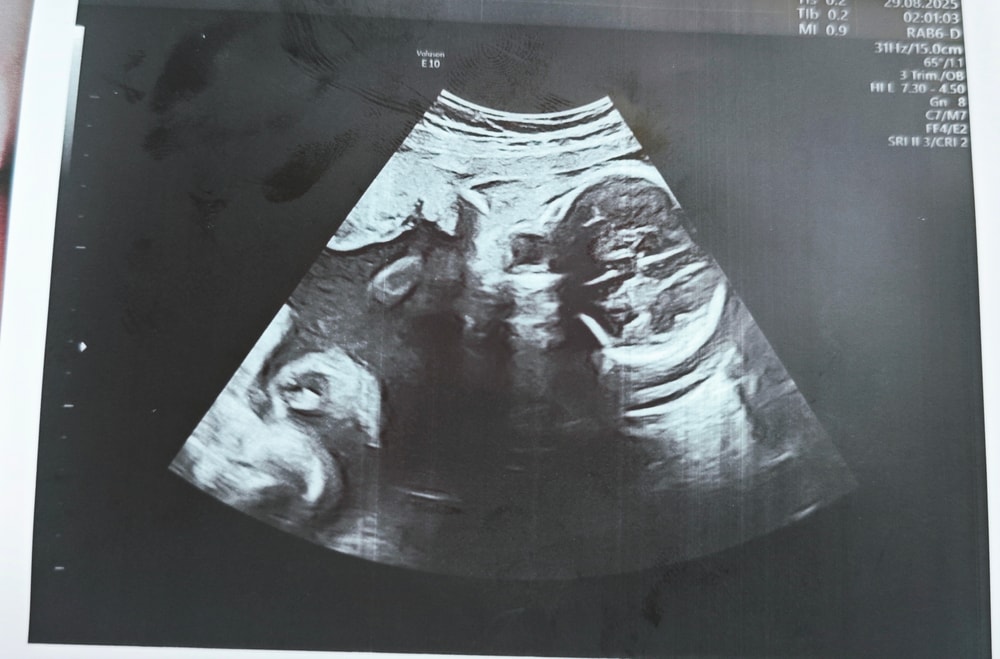

Сходила в частную клинику на УЗИ в 28 недель, сказали, что всё хорошо ттт, и дали фото. И вот когда я уже вышла с клиники и увидела фото, я вообще ничего не поняла. Это вроде голова, но вообще непонятно что где и выглядит жутковато...

Может тут кто-то разбирается или понимает что где на этих фото?

На последнем фото,под круглым тёмным пятном,белая полоска -глаз(веко закрыто) ну и профиль видно,рука правая приподнята.Ну я так увидела 😃 У меня тоже ни одной нормальной фотки не было с узи,лежал как то не удобно и руками ,ногами закрывался

Голова и ручки около лица. Голова у них на узи со всем содержимым видна🤣, потому и жутковато выглядит🤣🤣🤣